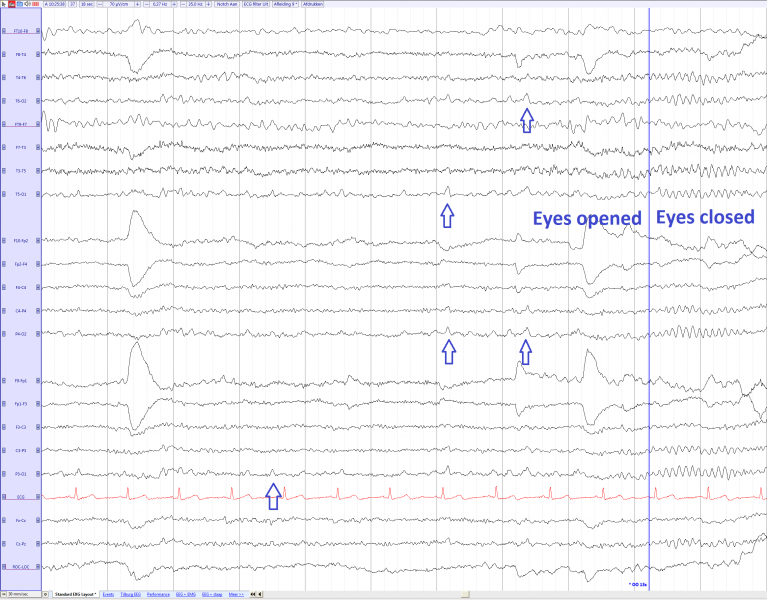

Lambda waves, absent during eyes closed

| current | 10:47, 22 February 2017 | 2,329 × 1,821 (301 KB) | EEGpedia (Talk | contribs) | Lambda waves, absent during eyes closed |